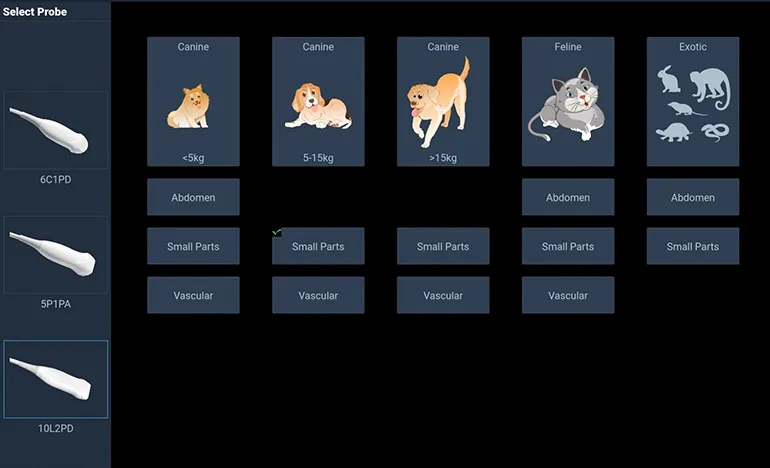

Готовые ветеринарные пресеты

Для проведения диагностики на УЗИ аппарате MV-3 Exp ветеринар может выбрать нужный пресет для конкретного исследования: кошки, собаки, лошади, свиньи, крупный и мелкий рогатый скот.

- полный набор инструментов для измерений

- специальные настройки для ветеринаров

- пояснения к программам с наглядной визулизацией